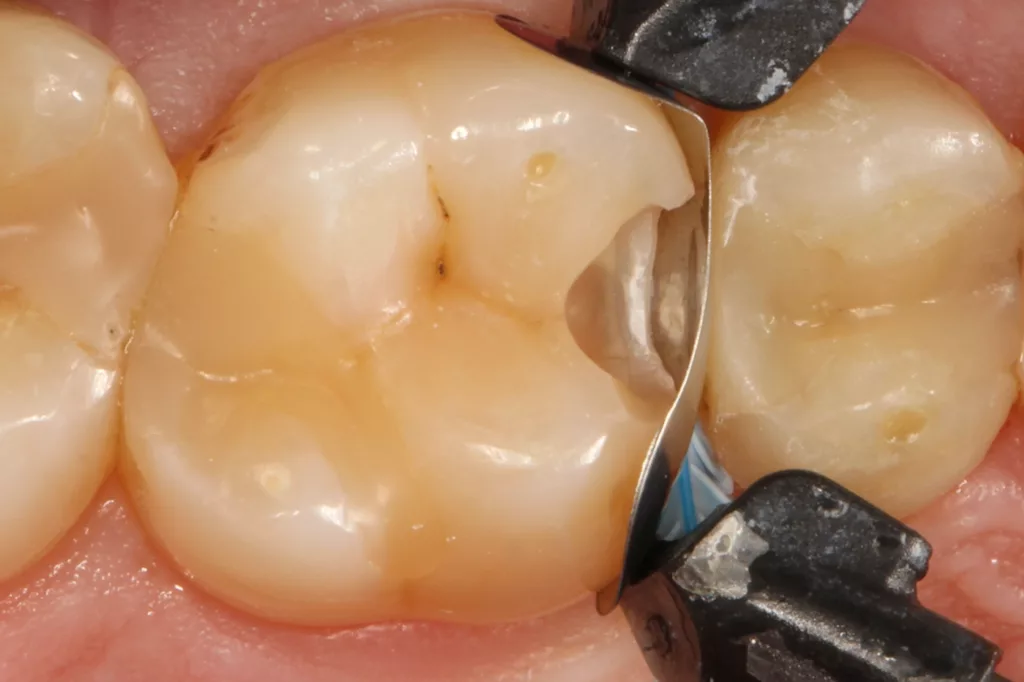

Fall 5: Versorgung einer okklusalen Kavität an einem unteren Molaren

Auch im Molarenbereich können Bulkflow-Materialien effektiv und ökonomisch eingesetzt werden, ohne Abstriche an der Ästhetik machen zu müssen, was der Fall des hier versorgten Zahnes 46 bei einer 22-jährigen Patientin zeigt. Die Abbildung 24 stellt die bereits präparierte und mit einem Einzelzahnkofferdam isolierte Kavität mit der Phosphorsäurekonditionierung der Schmelzränder (Gel Etchant, Kerr) dar. Die Entscheidung zur absoluten Trockenlegung fiel aufgrund der nicht so einfach kontrollierbaren Zunge und der vielen Schluckreflexe, was das Risiko einer ungewollten Speichelkontamination der Klebefläche unverhältnismäßig erhöhte.

Die Verwendung des Kofferdams ist generell eine sehr empfehlenswerte, aber keine zwingende Voraussetzung zur Etablierung einer suffizienten Kontaminationskontrolle [47,96]. Das bisher auch bereits verwendete Zwei-Schritt-Universaladhäsiv G2 Universal wurde hier in der selektiven Schmelzätztechnik angewendet, d.h., das Material arbeitet auf dem Dentin selbstkonditionierend (Abb. 25). Die bislang zu diesem innovativen Mehrflaschen-Universaladhäsiv publizierten Daten zeigen eine beeindruckende Performance, die den Vergleich mit sogenannten Goldstandards [98] wie einem Optibond FL nicht scheuen müssen [13,18,34,58,63,114,119,127,130]. Im nächsten Schritt wurden die einzelnen Höcker mit dem angenehm standfesten Flowable aufgebaut (Abb. 26). Die Abbildung 27 zeigt die komplett versorgte okklusale Kavität, die Abbildung 28 die Situation unmittelbar nach Ausarbeitung und Politur. Erneut beeindruckt die gute Farbadaptation.